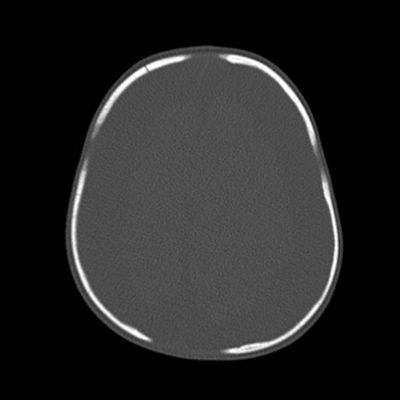

- B) Kemik pencerede frontal kemikte sağda nondeplase kırık

- Kalvaryal kırıklar: Tek başına istismar ilişkili kafa travması açısından spesifik olmasa da çoklu kırıklar istismara bağlı travma şüphesini artırır.